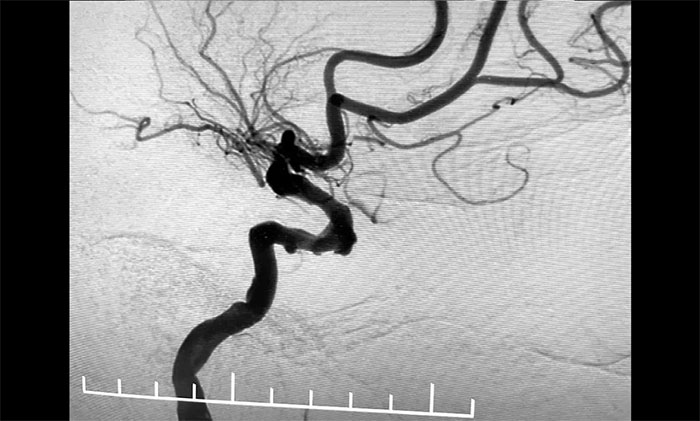

▲ 頸動脈狹窄合并左頸內動脈海綿竇段、床突段多發(fā)動脈瘤

接下來,左頸內動脈海綿竇段、床突段多發(fā)動脈瘤處理極具挑戰(zhàn)。由于C5、C6、C7段血管極度迂回曲折,類似“N”形,從C4、C5到C6之間的血管約成45°銳角,從C6至C7之間又是約30°銳角,可謂“山路十八彎”,而導絲又是極軟,每向前推進一毫米,都非常艱難。這種介入手術對術者的技術要求非常高,如果支架貼合不好,打開不良,還需要用導絲蠕動“按摩”,讓支架重新回到血管壁上。

▲ 血管極度迂曲,為手術帶來挑戰(zhàn)